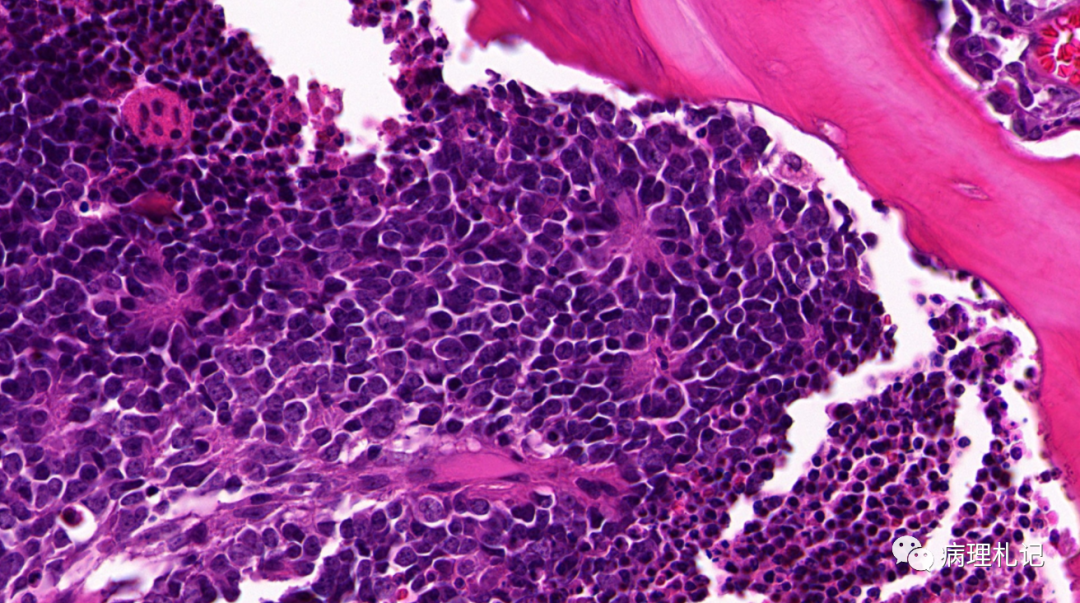

弥漫性神经纤维瘤中惊叹wagnermeissner小体